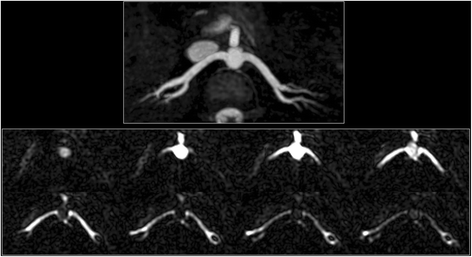

Example of cine FISS ASL for visualization and quantification of flow velocity in the left coronary arteries of a healthy subject. a 3-mm thick maximum intensity projection from oblique axial QISS MRA shows the left main and LAD coronary arteries (arrows). b Upper left frame shows graphical positioning of a 25-mm thick adiabatic inversion RF pulse through the aortic root which overlaps the sinuses of Valsalva and the ostium of the left main coronary artery. Remainder of frames (seven out of 32 acquired) acquired with cine FISS ASL (oblique axial orientation) show the progression of the labeled bolus (arrows) through the left main and LAD coronary arteries. The time between successive frames was 37.1 msec and the mean flow velocity between 444 msec and 615 msec after the R wave was 16.4 cm/s. c QISS MRA of the LAD (arrows) in an oblique coronal view. d MIP of three overlapping cine FISS ASL slices acquired in an oblique coronal plane through the LAD (eight frames displayed of 32 acquired). Blood in the aortic root was labeled in diastole, 580 msec after the R-wave (upper left frame). The labeled bolus (arrows) can be visualized as it progresses through nearly the entire length of the LAD. e The proximal LAD (inset, arrow) is seen in cross-section with 2D phase contrast using through-plane flow encoding (30 cm/s), permitting quantification of the diastolic flow velocity (which was similar to that measured by cine FISS ASL). f 2D phase contrast scan acquired with right-to-left flow encoding along the length of the LAD shows only faint, incomplete visualization of the vessel due to partial volume averaging and in-plane flow saturation

In healthy subjects, there was excellent correlation between maximal aortic flow velocities measured by cine FISS ASL and 2D phase contrast (r2 = 0.959, p < 0.001). Mean coronary flow velocity, measured with cine FISS ASL over a ≈ 209 ± 97 msec (mean ± sd) span of diastole was 11.7 ± 3.0 cm/s. The cine FISS ASL contrast-to-noise ratio between the coronary artery and background was 16.5 ± 6.1.